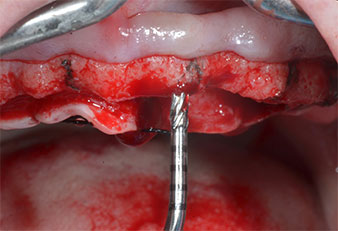

Uno strumento piezoelettrico (Piezomed I1) a forma di fiamma, rivestito in diamante, è stato usato per contrassegnare le posizioni dell'impianto e per eseguire una preparazione pilota (Fig. 3). Si è prestato attenzione a utilizzare un movimento verticale ascendente e discendente, con potenza ridotta, irrigazione completa e bassa pressione (inferiore a 300 g). Successivamente è stato applicato uno strumento pilota (Piezomed I2A/I2P) per l'ingrandimento iniziale delle sedi dell'impianto del diametro di 2 mm (Fig. 4), seguito da un inserto da 3 mm (Fig. 5).

Strumenti Piezomed I2A/I2P

Fig. 4: il prossimo passo è l'allargamento pilota con gli strumenti Piezomed I2A/I2P, che vengono applicati con un movimento orizzontale rotatorio.